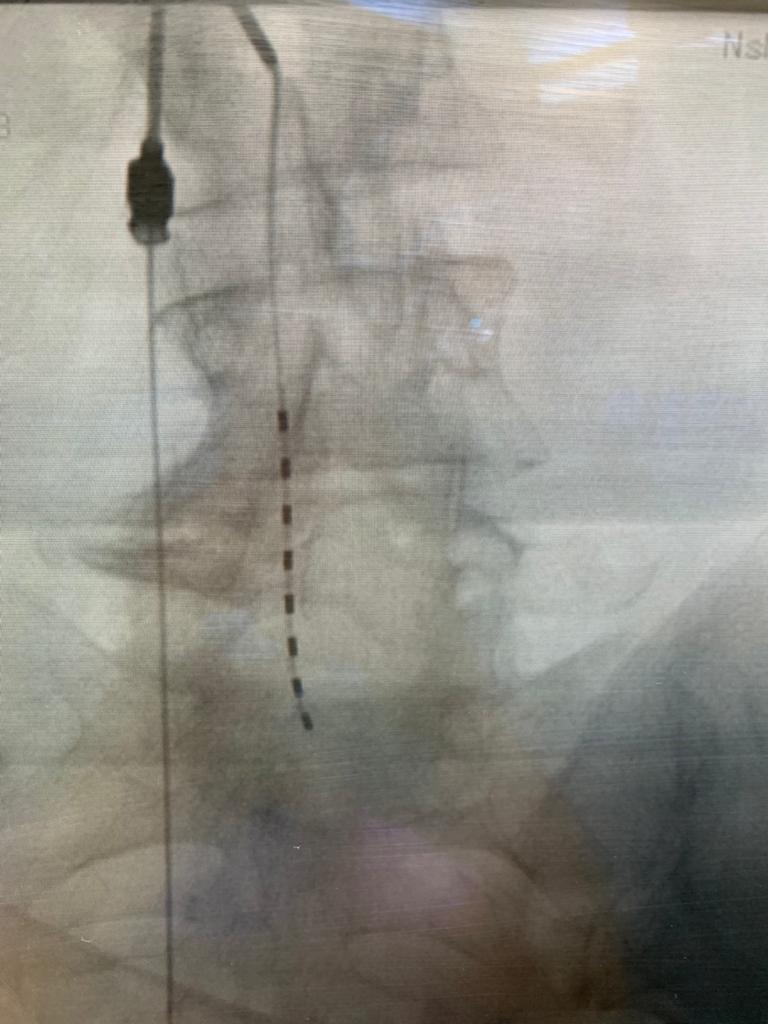

Medicínskym garantom a hlavným školiteľom bol MUDr. Róbert Rapčan, PhD, MBA, FIPP, ktorý sa pri výučbe zameral na endoskopickú diskektómiu a epiduroskopiu, špičkové miniinvazívne a endoskopické výkony aplikované pri ošetrení fragmentov vysunutých medzistavcových platničiek a epidurálnej fibrózy. Účastníkmi workshopu boli o. i. talianski špecialisti Dr. Riccardo Calimici a Dr. Felice Occhigrossi, ktorí veľmi pozitívne zhodnotili vysokú kvalitu výučby a ocenili jej hodnotný prínos a prospešnosť pre vlastnú klinickú prax. Certifikovaný seminár prebehol ako„live case surgery“, t. j. priamo v priebehu operačných výkonov na pracovisku EuroPainClinics v Košiciach.